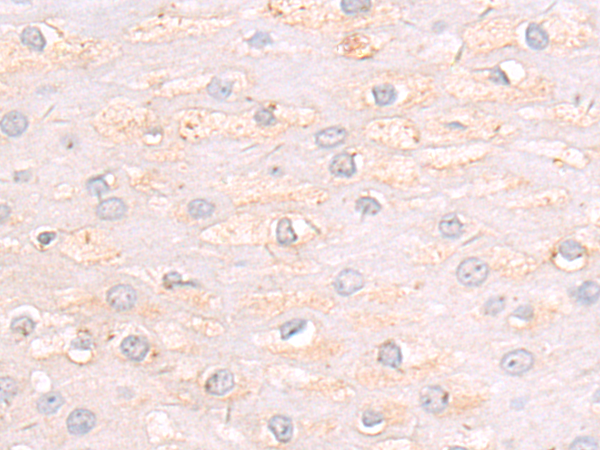

分类: 科研抗体货号: P07154别名: Car3; CAIII应用: WB,IHC反应种属: Human, Mouse, Rat